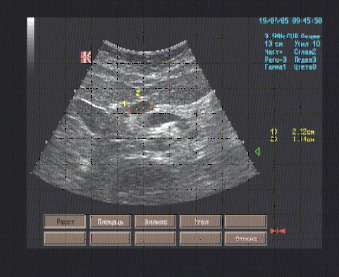

Поджелудочная железа обычной формы, с чёткими ровными контурами, толщина головки 25 мм., тела - 15 мм., хвоста – 27 мм., эхоструктура изоэхогенная, неоднородная за счёт анэхогенной полости в проекции переднего отдела головки на границе с телом размерами 22 х 15 мм., имеющей правильную овальную форму, ровные чёткие контуры, однородное содержимое.

Эхографические признаки простой кисты головки поджелудочной железы.